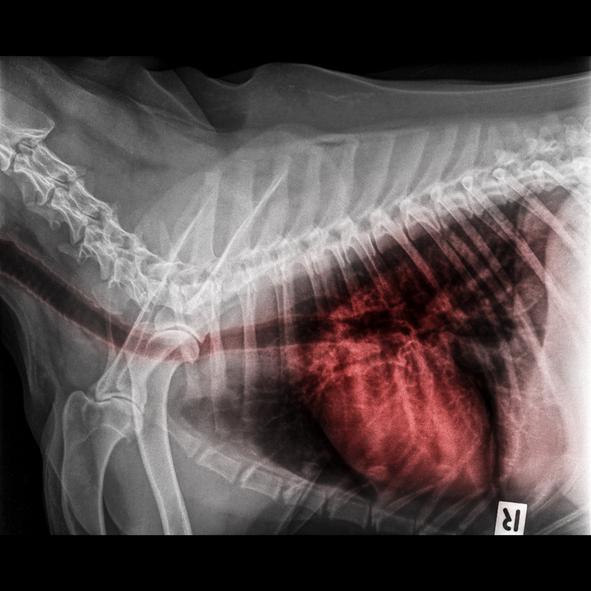

El edema pulmonar cardiogénico en perros es el que se origina debido a una enfermedad cardíaca. Cuando el corazón falla se produce un reflujo de sangre hacia los pulmones, el hígado, las extremidades, etc. Este reflujo aumenta la tensión en las venas, que es lo que hace que el líquido se filtre a pulmones o cavidad abdominal. Con líquido en los pulmones, el perro tose. Así, el edema pulmonar indica insuficiencia en la parte izquierda del corazón. En cambio, cuando la lesión está en la parte derecha, el líquido se acumula en el abdomen, causando ascitis y edemas en las patas y, también, en la cavidad torácica, lo que se conoce como derrame pleural. Si el líquido se acumula en los bronquiolos de los pulmones el perro puede presentar una expectoración de líquido rojizo y espumoso. Los perros con este problema es habitual que presenten cardiomegalia y el edema pulmonar. La cardiomegalia es el aumento de tamaño del corazón,

Se utilizan pruebas diagnósticas como la auscultación, la radiografía de tórax o la ecografía, además de la analítica sanguínea. El electrocardiograma, el examen de la orina y la medición de la presión arterial también son pruebas importantes para saber si un perro tiene edema pulmonar. En los animales más graves hay que tener especial cuidado, ya que cualquier manipulación puede agudizar la crisis respiratoria.